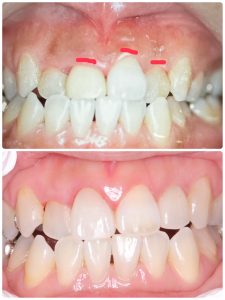

次は昨年セットした方

病巣も治癒、マージンラインの整合制がテーマ

歯冠延長術やら駆使